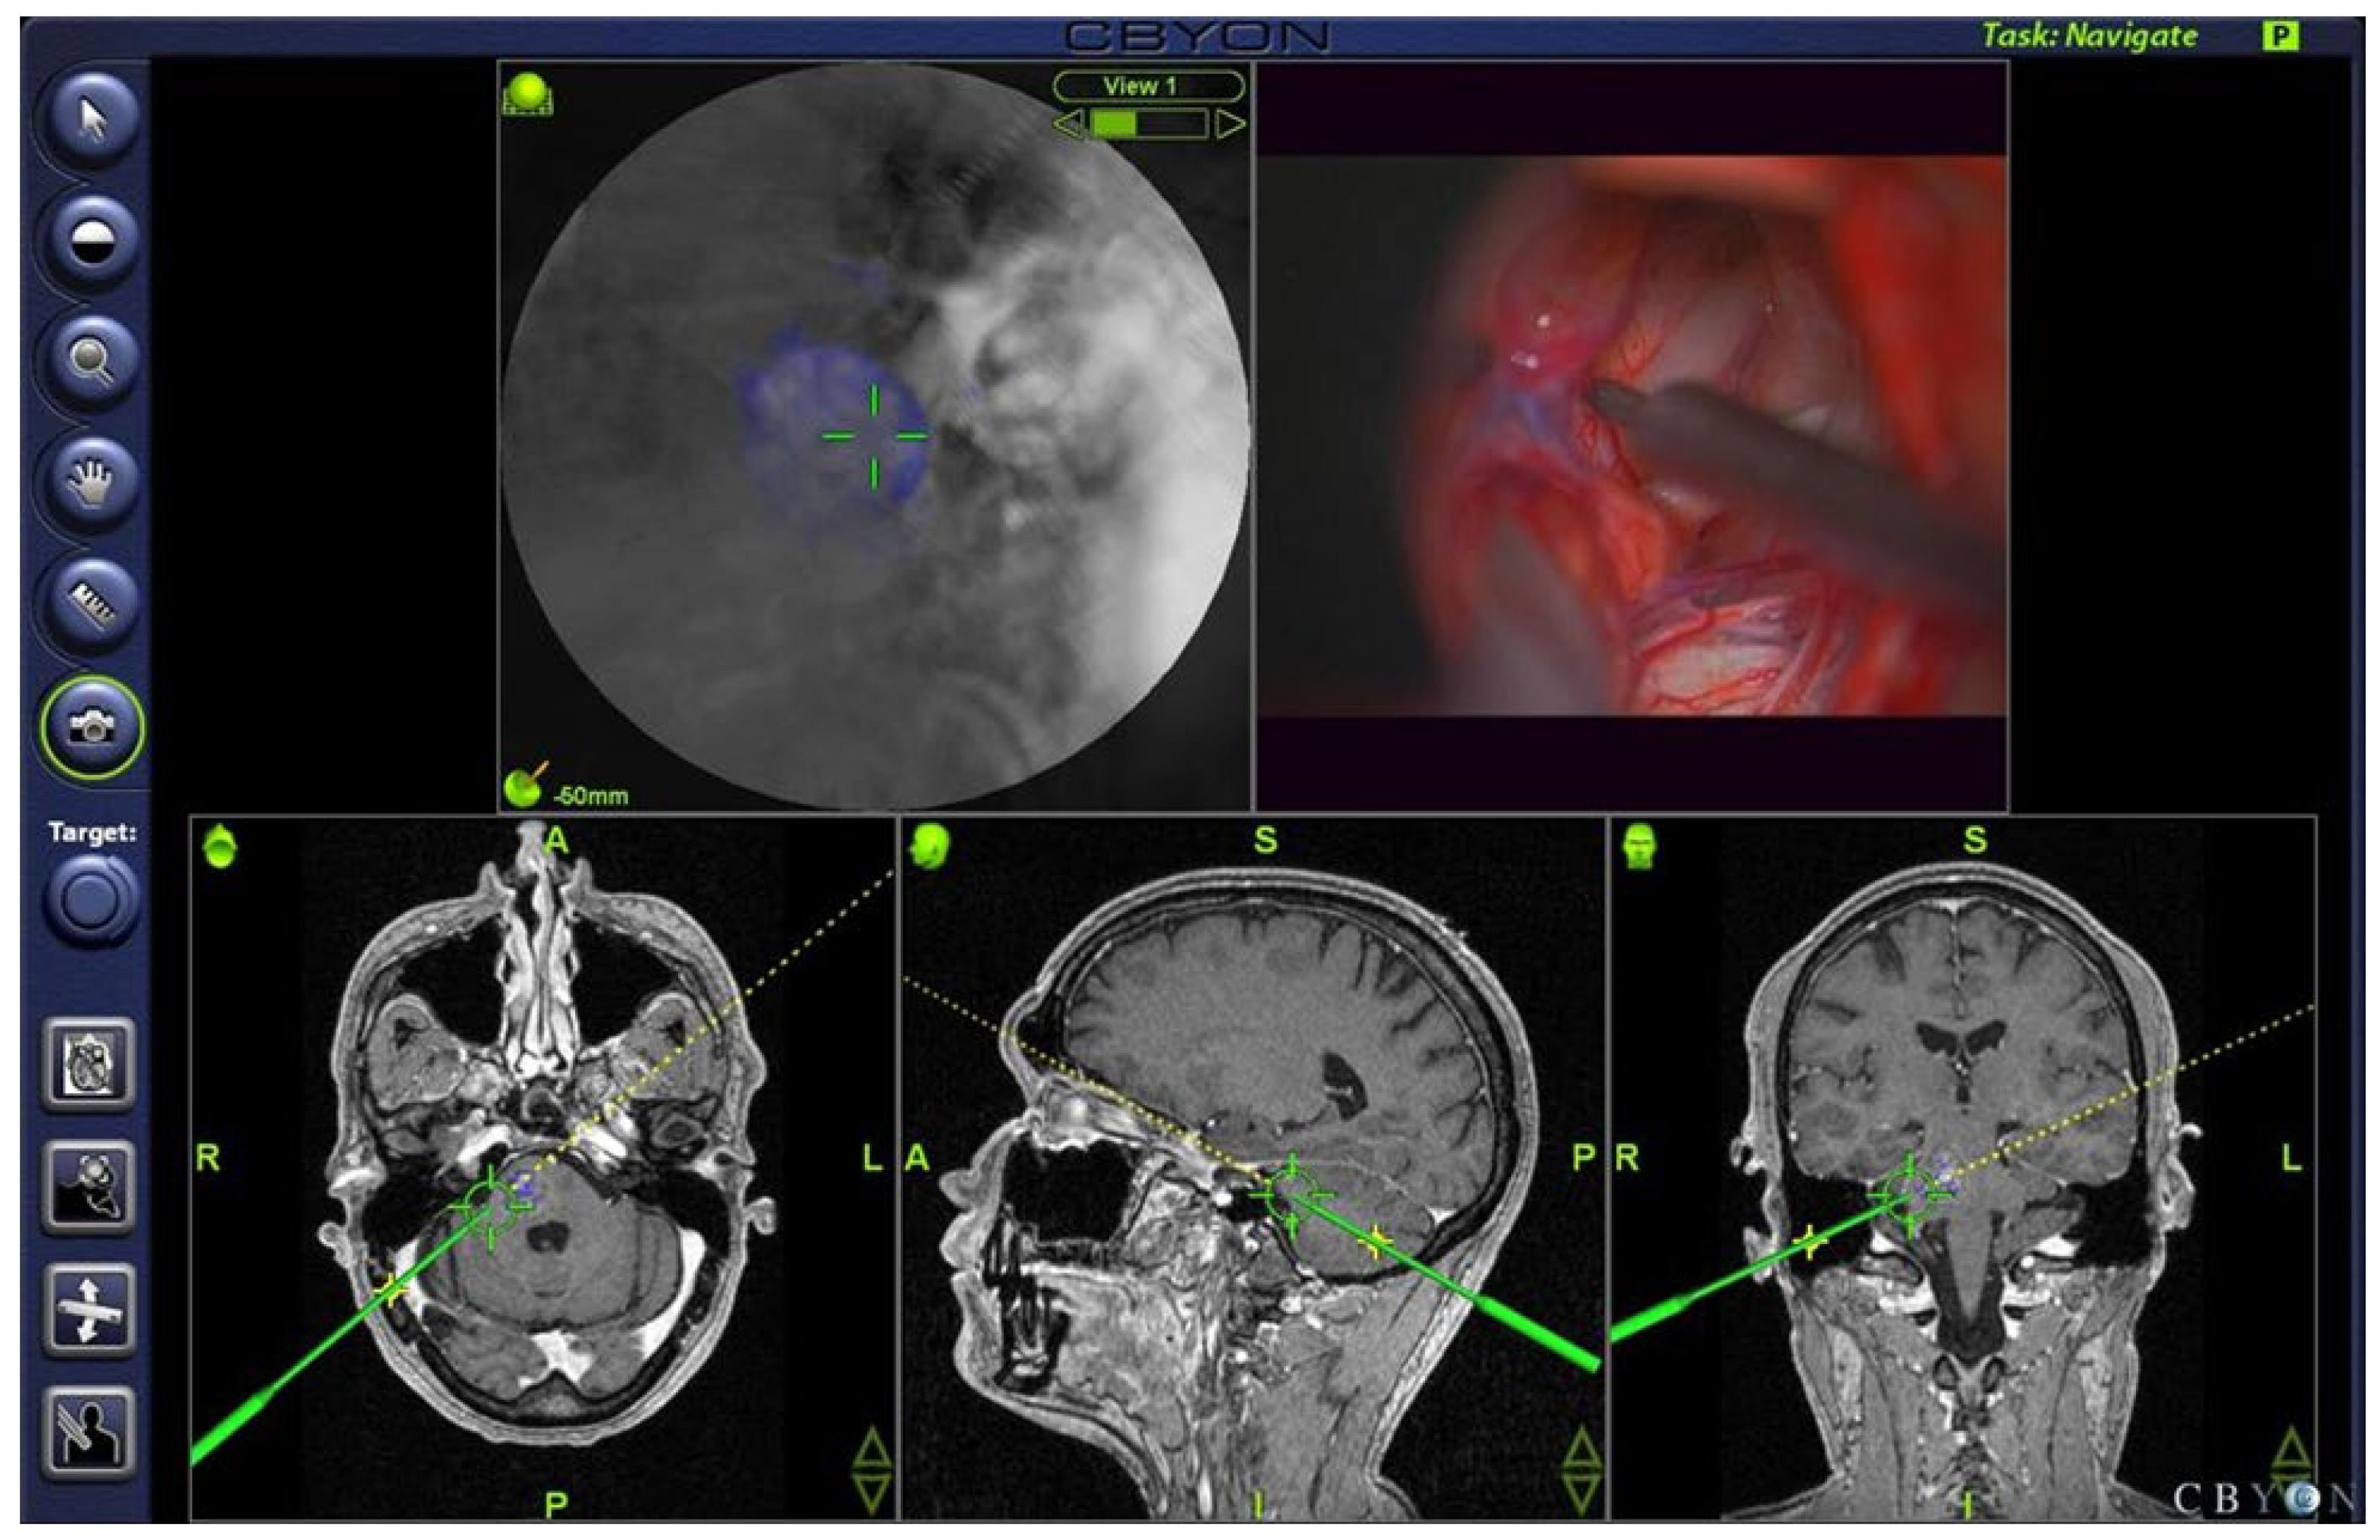

All operations were planned preoperatively and then performed using neuronavigation (CBYON™—Med-Surgical Services Inc., Sunnyvale, CA, USA) to select the shortest path to the deep-seated lesions that were not visible at the brainstem surface. The CBYON™ Neuronavigation System provides three-dimensional (3D) volumetric image rendering and allowed for the modulation of the opacity of tissue layers, making the brainstem transparent on the navigation screen (Figure 2). Intraoperative electrophysiological mapping of the brainstem surface was performed during all procedures to find the safest entry point. Continuous intraoperative monitoring (IOM) during the procedure included the recordings of motor-evoked potentials (MEP) and sensory-evoked potentials (SEP) of the lower and upper limbs, and the recordings of auditory-evoked potentials of the brainstem (BAEP) and the MEP of the facial nerve in all cases. Depending on the level of the lesion in the brainstem, electromyography (EMG) and MEP recordings of the following cranial nerves (CN) were also performed: CN III for midbrain lesions, CN VI for pontine lesions, and CN IX–XII for medulla oblongata lesions. MEPs were recorded continuously with transcranial electrical stimulation via corkscrew electrodes positioned at CZ and C3 +1 cm lateral or C4 +1 cm lateral for the facial nerve and C3 and C4 for the upper and lower extremities. Stimulations were always contralateral to the affected side for 0.5 milliseconds, with five pulses and a voltage range of 130–300 V for cranial nerves (CN) or 300–500 V for upper and lower extremities, always with 2 milliseconds between stimuli. MEPs were recorded from needles placed in the affected target muscles. Baseline values for SEP and MEP were obtained before craniotomy. Direct stimulation of the brainstem was performed using a bipolar probe with 0.3 to a maximum of 3 mA, 3.2 to 5.2 Hz continuous stimulation, and a stimulation duration of 0.1 milliseconds.

After the exposure of the brainstem, systematic mapping of its surface was performed to determine the safest entry point. Several authors have described in detail different methods of brainstem mapping [28,42,43,44]. We recommend performing brainstem mapping even in the presence of discoloration of the brainstem surface. In addition to standard brainstem mapping and monitoring, we performed transcranial electrical stimulation in all cases to monitor motor evoked potentials (MEP) of muscle groups of the arms, legs, and relevant CNS in each individual procedure. This is highly recommended, especially during the approach to the lesion, to ensure that no deficits are caused during the approach to the lesion. A voxel-based neuronavigation system with 3D image volume display and a feature that allows for a variation in tissue layer opacity (CBYON™—Med-Surgical Services Inc., Sunnyvale, CA, USA) was used as needed. An “endoscopic view” allowed for the direct localization of the lesion on BS, especially in cases where the lesion did not reach the surface (Figure 2).

Figure 2. Screenshot of intraoperative neuronavigation (CBYON™—Med-Surgical Services Inc., Sunnyvale, CA, USA) showing the “virtual endoscopic” view (top left image) through the tip of the pointer (top right image) with 3D volume image rendering and modified opacity of the tissue layers, revealing the deep-seated cavernoma (blue) in the pons and guiding the neurosurgeon to a safe entry point.